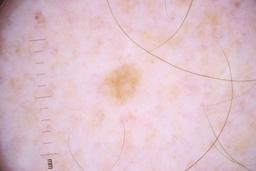

ISIC_4077341

- Challenge 2020: Training

- IP_1969685 IL_9238622

Clinical

| Field | Value |

|---|---|

| acquisition_day | 1 |

| age_approx | 50 |

| anatom_site_1 | Trunk |

| anatom_site_2 | Anterior trunk |

| concomitant_biopsy | False |

| dermoscopic_type | contact non-polarized |

| diagnosis_1 | Benign |

| diagnosis_confirm_type | serial imaging showing no change |

| family_hx_mm | False |

| image_type | dermoscopic |

| lesion_id | IL_9238622 |

| patient_id | IP_1969685 |

| personal_hx_mm | True |

| sex | male |